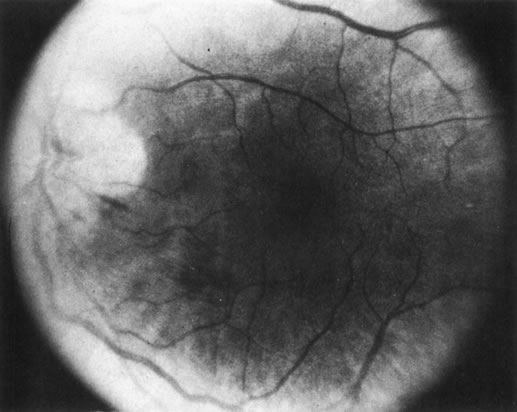

Some retinal dystrophies and degenerative processes can simulate a retinochoroiditis. Vitreous cells may occur in cases of retinitis pigmentosa. Pigmented paravenous retinochoroidal atrophy has a distinctive pattern of pigmentary deposits surrounding retinal veins; it may occur as an idiopathic degenerative disorder or sometimes as a sequela of ocular sarcoid. Fundus flavimaculatus is a rare autosomal recessive dystrophy that is usually detected in the third decade of life. It produces typical comma-shaped, yellowish retinal pigment epithelial opacities in the posterior pole, but it does not involve the macula. It can simulate a diffuse choroiditis (Fig. 24). Myopic degeneration can produce small, white, posterior pole spots that can simulate a posterior choroiditis. Peripheral fundus “paving stone” degeneration is rarely confused with an inflammatory process. These lesions show no evidence of retinal or vitreal inflammation and are quite common.54

Fig. 24. Fundus flavimaculatus. Note comma- or fish-shaped yellowish Figures at the level of pigment epithelium.